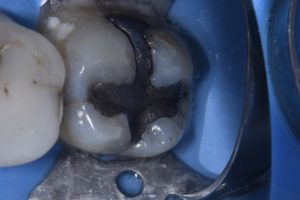

February 7, 2020 Large complex amalgam removal and core stabilization attempt using a single shade of Kulzer Venus Pearl A3.5. Tints: Voco Final Touch. #Kulzer #VenusPearl #Voco #FinalTouch #Dermadam #Ultradent Previous Post Next Post